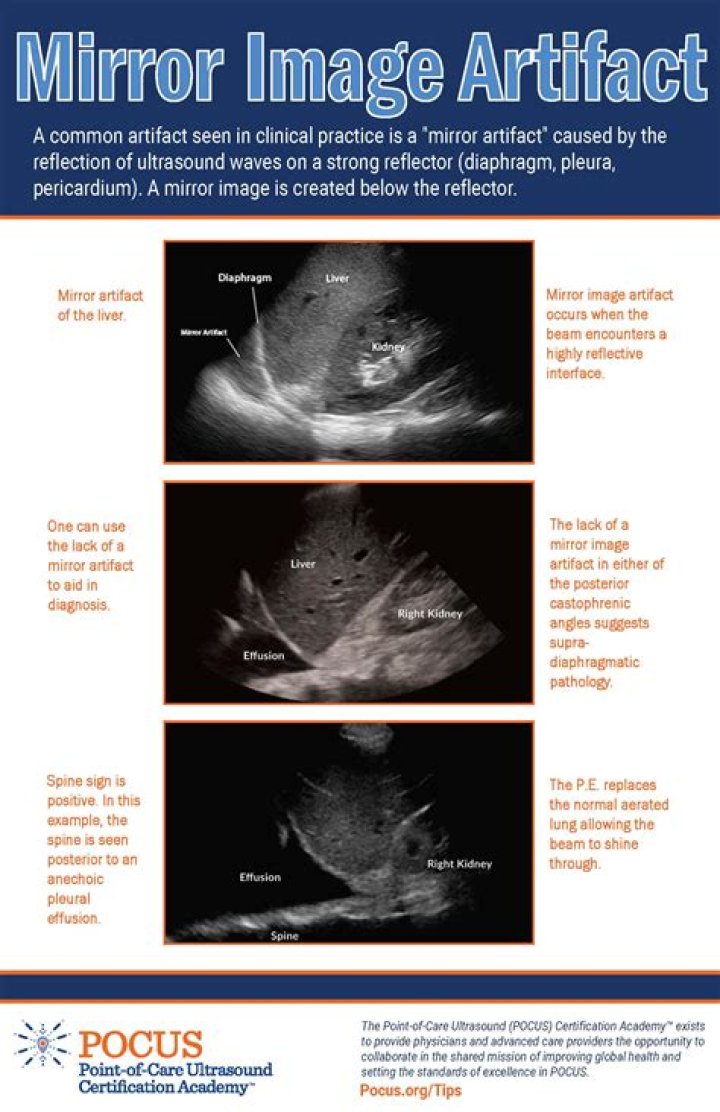

What causes mirror image artifact

Mirror image artifacts occur when the transmitted pulse and returning echo reflect off of a highly reflective interface (an acoustic mirror) and change direction before returning to the transducer, thereby breaking this assumption.

Mirror image artefact is one of the beam path artefacts. These occur when an ultrasound beam is not reflected directly back to the transducer after hitting a reflective surface, but rather takes an indirect return journey.

Mirror artifacts occur when there is a strong difference in tissue velocity. When reflective echoes bounce back and forth, the structure is flipped. Mirror artifacts are friendly artifacts that let us exclude pleural effusion because of the reflection of the liver’s image through the diaphragm.

Where does the mirror artifact commonly occur?

A common mirror image artifact occurs at the interface of the liver and the diaphragm in abdominal imaging. In one direction, the ultrasound beam correctly positions the echoes emanating from a lesion in the liver.

Mirror artifacts are produced by the reflection of ultrasound waves after they propagate through a structure and encounter a strong and smooth interface capable of acting as a mirror.

Mirror image artifacts occur when the transmitted pulse and returning echo reflect off of a highly reflective interface (an acoustic mirror) and change direction before returning to the transducer, thereby breaking the assumption of a straight path.

How can the sonographer eliminate a mirror image artifact if it occurs?

Mirror image artifacts, which also occur with color Doppler US, may be reduced by decreasing the gain or changing the angle of insonation.